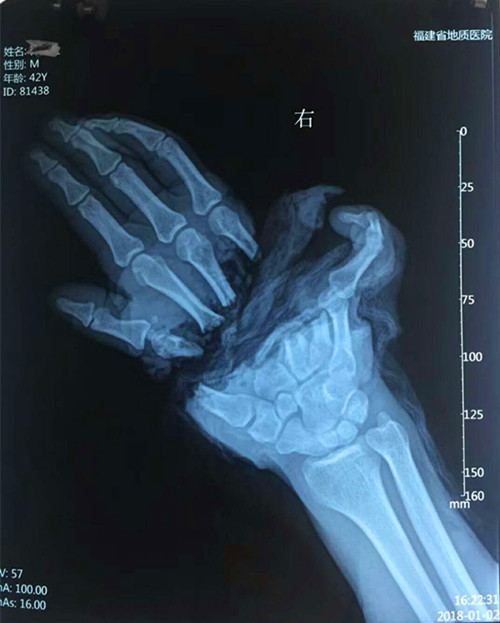

患者,许某某,男性,42岁,长乐某工厂职工,因在做工时被机器绞伤,右手掌完全离断。经诊断分析:手部掌骨粉碎,血管、神经、肌腱、肌肉、皮肤绞烂撕脱,伤情严重,再植难度大,手术时间长。

患者入院后,在骨科郑国钦主任带领下,积极完善术前准备后,第一时间为患者在麻醉下行“断掌清创探查再植”手术,术中固定粉碎的骨块,重建屈、伸指肌腱功能。在显微镜下探查血管、神经,发现主要血管撕脱伴管壁碎裂、管腔内栓塞,术中予移植多根血管,修复离断掌体的供血动静脉,同时修复断裂的神经。术中力排各种困难与风险,医护人员经过长达12小时的协同奋战,当松开患者右上臂气囊止血带后,患者离断的右手掌皮肤瞬间由苍白转为红润。当再植手术成功告知患者及家属手术顺利时,他(她)们担心忧愁的脸上均露出了宽慰的笑容。